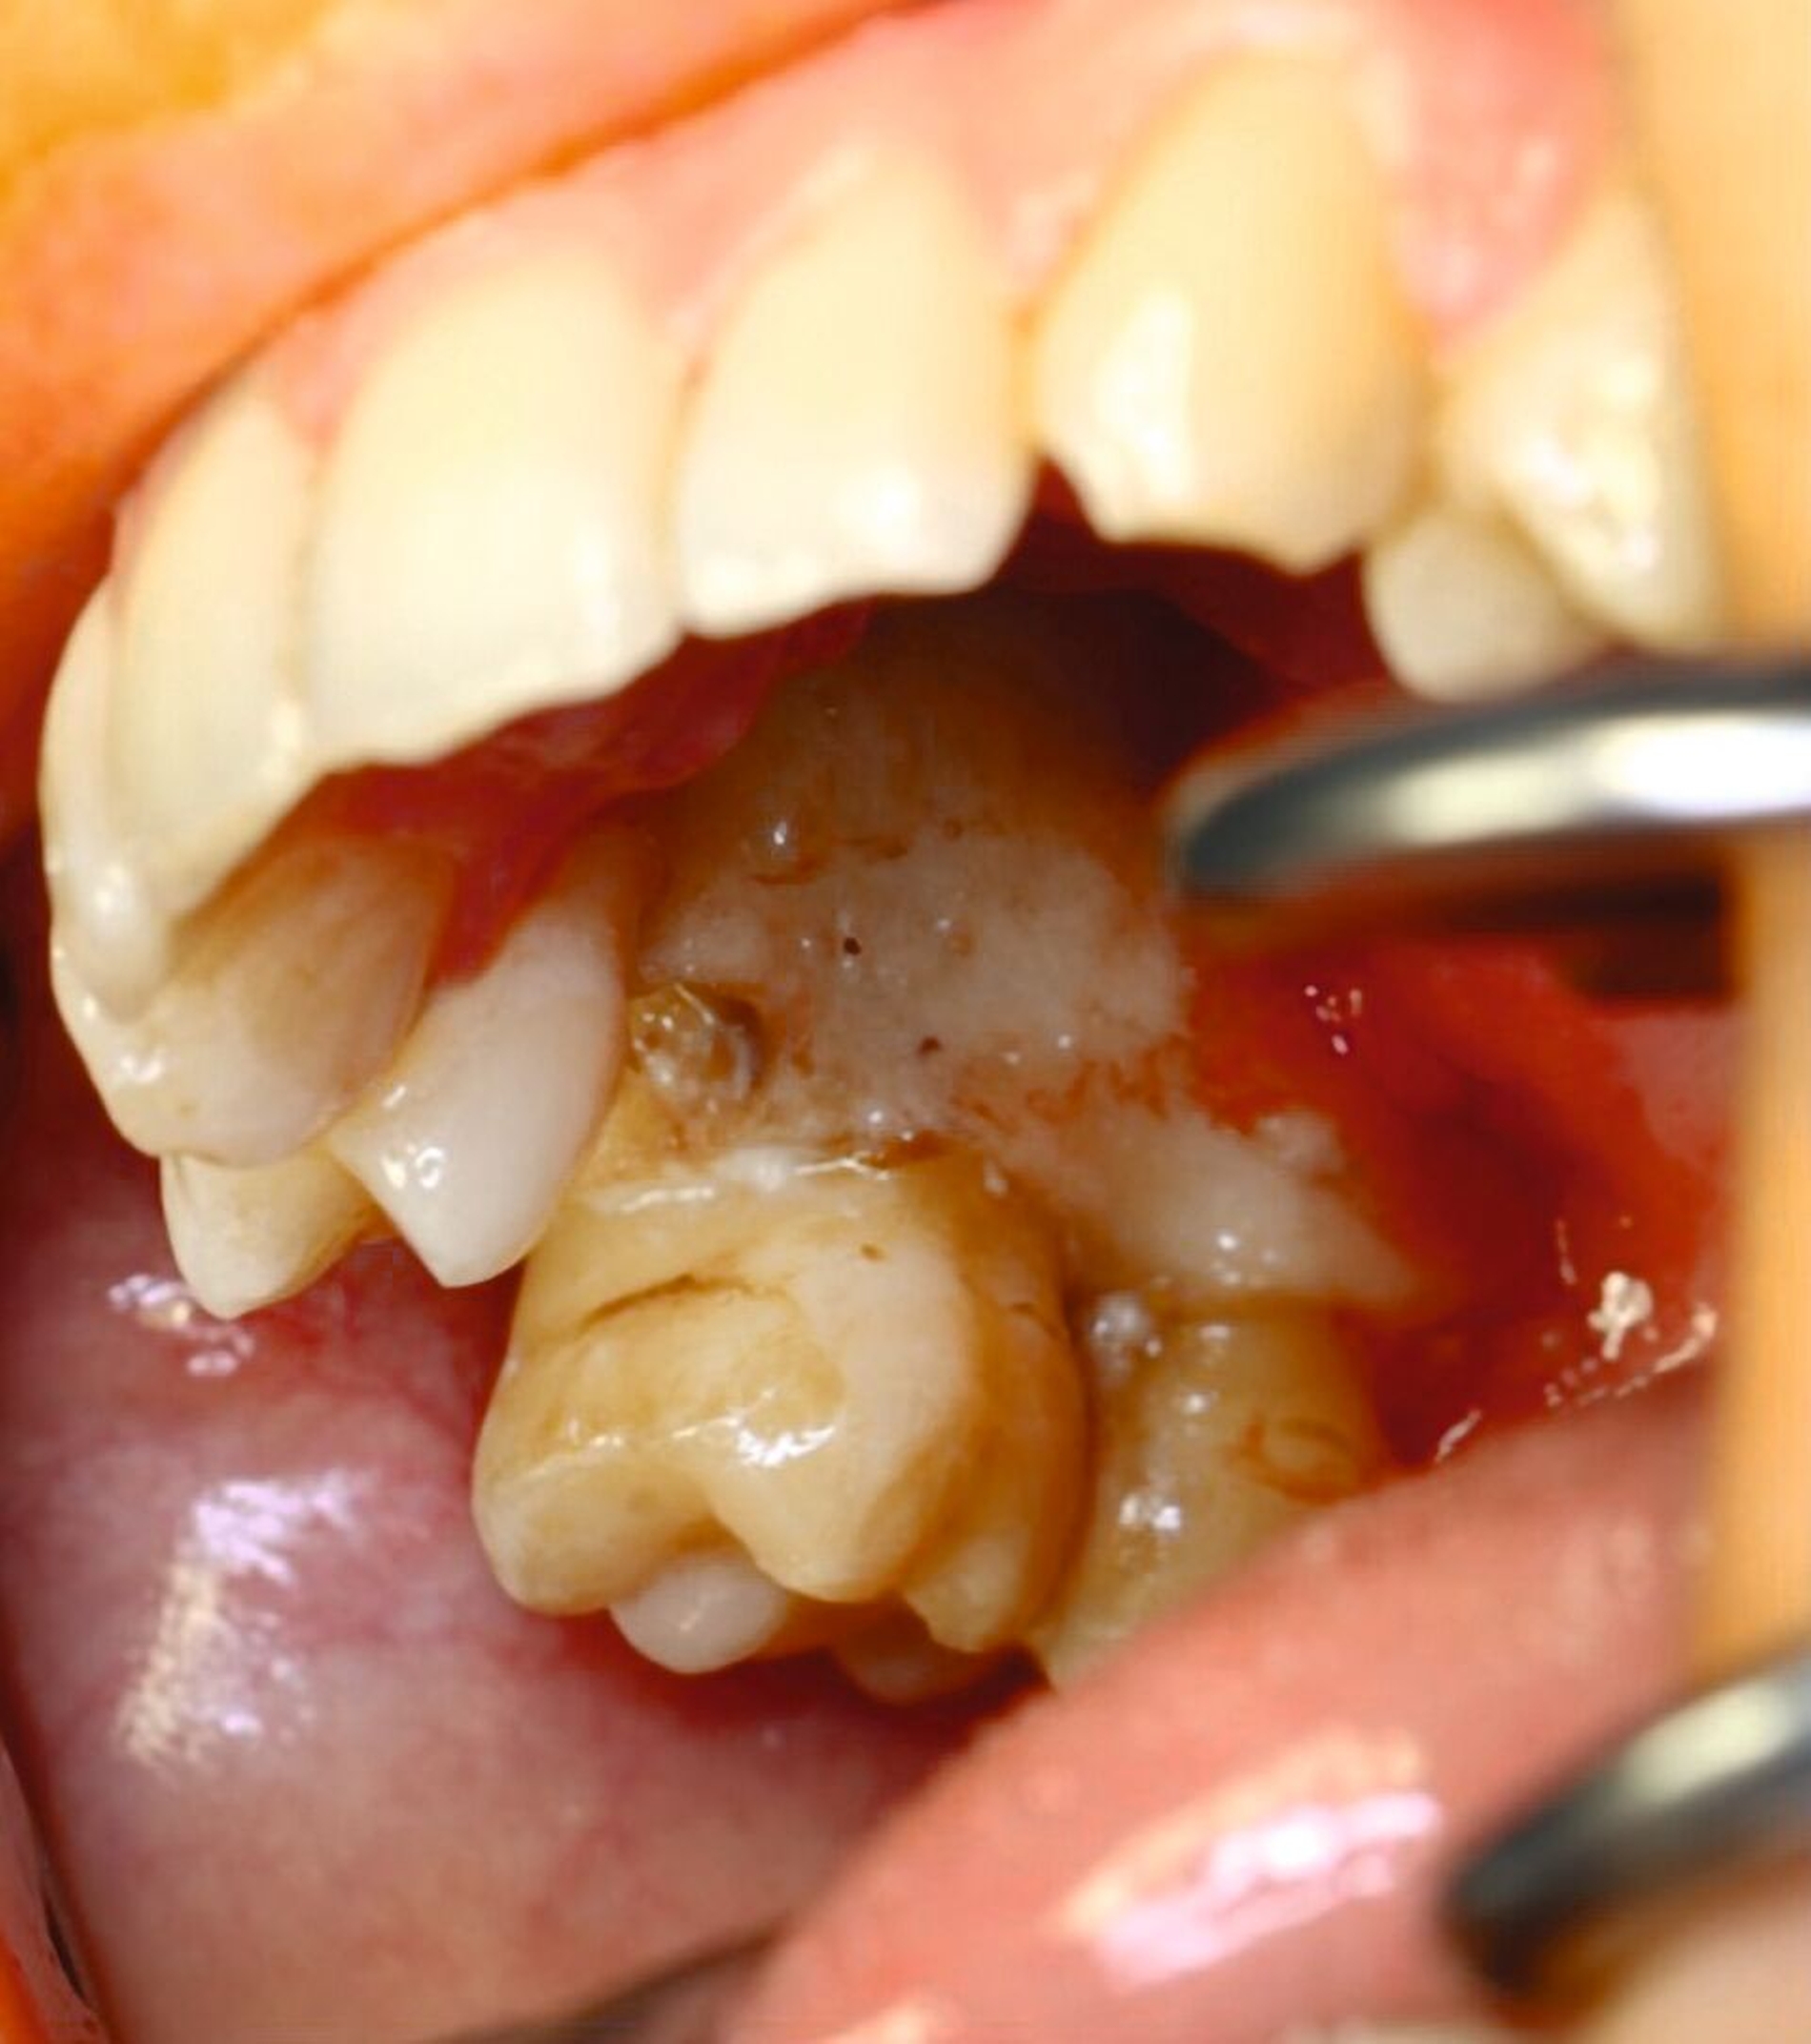

Im Verlauf der nächsten vier Wochen zeigte sich keine weitere weichgewebige Granulation (Abbildung 4). Vier Monate nach dem Spülunfall grenzte sich in der DVT-Bildgebung ein Sequester regio 15/16 ab (Abbildung 5), weshalb die Patientin nun zur operativen Sequesterotomie vorbereitet wurde. Der Sequester ließ sich zusammen mit Zahn 16 im operativen Eingriff vollständig und komplikationslos entfernen (Abbildung 6).